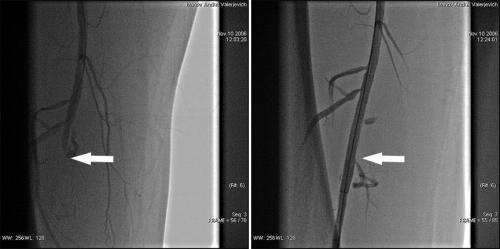

Установить диагноз ОААНК помогают следующие инструментальные методы диагностики: запись пульсовой волны, дуплексное сканирование, допплерометрия, нагрузочные тесты, при необходимости — магнитно-резонансная и компьютерная томография, аортоартериография . Рентгенконтрастная ангиография является золотым стандартом диагностики патологии артериального русла, а также визуализирует возможности для эндоваскулярного вмешательства непосредственно во время процедур . Также для диагностики применяется радионуклидный метод трехфазной сцинтиграфии конечностей с остеотропным радиофармпрепаратом «99mТспирфотех» .

Для лечения атеросклероза артерий нижних конечностей используются также баллонная ангиопластика и стентирование , позволяющие расширить просвет сосуда. Однако возможность применения данных методов ограничена. Они эффективны лишь в случае, если окклюзия наблюдается на отдельном, сравнительно коротком участке артерии.

Что это? Внутрисосудистый метод лечения ишемии нижних конечностей*. Во время процедуры все внутрисосудистые инструменты (баллоны, стенты и т.д.) попадают в артерии ног через прокол на руке или ноге с помощью длинных пластиковых трубок (катетеров), перемещаясь по «рельсам» (проводнику).

Как это делается? Как и при ангиографии, к месту закупорки или сужения артерии подводят трубку (проводниковый катетер). Далее проводником (тонкой металлической струной со специальным покрытием, заведенной через просвет катетера) хирург проходит через пораженный сегмент сосуда. По проводнику в область закупорки/сужения устанавливают баллон, который затем раздувают. Таким образом восстанавливается проходимость артерии. Для поддержания формы артерии в ряде случаев (не всегда) имплантируется металлический каркас – стент. Он также доставляется к месту сужения на баллоне, двигаясь по «рельсам» (проводнику). В конце процедуры врач контролирует кровоток по артерии, положение стента с помощью ангиографии. После завершения процедуры на место пункции накладывается давящая манжета или повязка, которая позволяет отверстию в артерии закрыться.

Всем ли пациентам с заболеваниями артерий нижних конечностей можно выполнить подобное вмешательство? В большинстве случаев (в 70-80%) больным с ишемией нижних конечностей можно помочь, выполнив ангиопластику. Однако, от 20 до 30% из них потребуют более серьезного и сложного вмешательства — шунтирования (создание нового сосуда взамен «заросшего») или эндартерэктомии (восстановление просвета артерии путем удаления из нее атеросклеротической бляшки). Это так называемые «открытые операции», которые, в противоположность внутрисосудистым вмешательствам, требуют более серьезной подготовки, общей или проводниковой анестезии, значительно более длительной реабилитации. Выбор той или иной методики вмешательства индивидуален, зависит от большого числа нюансов, осуществляется врачами-специалистами и всегда обсуждается с пациентом.

Безусловно, разные модели стентов отличаются по своим техническим характеристикам. Однако крупные сравнительные исследования стентов разных производителей отсутствуют. На основании анализа публикуемых результатов стентирования артерий нижних конечностей трудно прийти к однозначному заключению о том, влияет ли выбор модели стента на результат операции. Существующие рекомендации оставляют этот вопрос на усмотрение хирурга. Стенты со специальным покрытием крайне редко используются при ангиопластике артерий нижних конечностей, поскольку их преимущества перед обычными стентами в этой категории больных убедительно не доказаны. Результат внутрисосудистого вмешательства на артериях нижних конечностей главным образом зависит от особенностей поражения сосуда (протяженность и локализация закупорки, состояние сосудистого русла «выше» и «ниже по течению») и тяжести симптомов заболевания.

- Ангиография – сложный инвазивный метод исследования сосудов. В случае коронарных артерий – коронарография. Самый точный метод исследования сосудов на предмет атеросклеротических бляшек. Через специальный катетер, который вводится в бедренную артерию, подается контрастное вещество, которое моментально заполняет исследуемые сосуды. Выполняя рентгеновские снимки в нескольких проекциях, возможно, определить степень сужения сосудов или их полную облитерарацию (закупорку). Метод исследования проводится в стационарных условиях под местной анестезией.